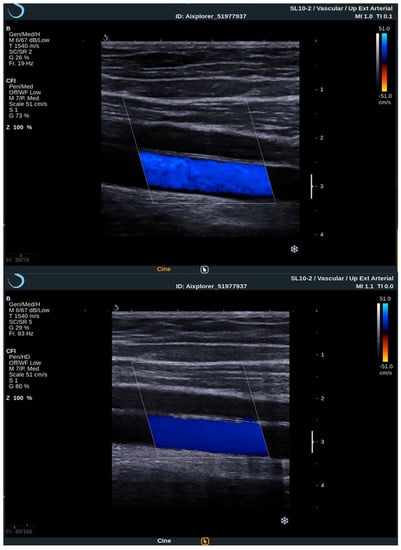

In addition to conventional, Doppler and contrast-enhanced ultrasonography, elastography techniques are another area where ultrasound is being increasingly used, this time to assess the elastic properties of the insonated tissue. There are two types of ultrasound elastography: strain and shear wave elastography (SWE). Strain elastography is performed by manual compression using the transducer, which then produces an image based on the resulting displacement of the tissue caused by the compression. However, it is difficult to measure the exact amount of the applied force during compression, resulting in the method being difficult to standardize. Additionally, the absolute elasticity values cannot be calculated, and only qualitative results can be obtained. Unlike strain elastography, SWE is a type of ultrasound elastography where the elastic properties of the insonated tissues can be expressed both qualitatively and quantitatively (Figure 1 and Figure 2) [22].

Figure 2. Another example of an ultrasound examination with shear wave elastography of a segment of the CCA, this time in the transverse view. A carotid artery plaque is visible in the wall of the CCA and displayed with B-mode ultrasound at the bottom and shear wave elastography at the top. In this figure, the elastic properties of the examined tissues are displayed both qualitatively and quantitatively. Quantitative measures are visible on the right-hand side of the picture, measured using two regions of interest, one centered over the plaque and another over the adjoining soft tissues, and an elasticity ratio between the two is calculated by the ultrasound device.